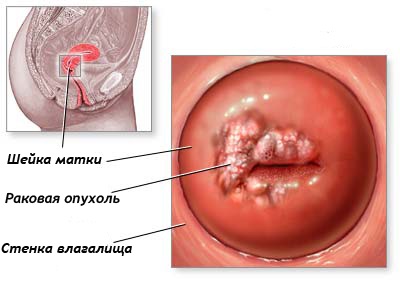

Cancerul de col uterin este cea mai frecventa malignitate a sistemului de reproducere feminin. afectează în principal femeile după menopauză, au deja fundal și boli precanceroase (polipi de col uterin, eroziunea, leucoplazie).

cancerul de col uterin

Această metodă, în special, folosind agenți de contrast, permite determinarea limitelor de distribuție, localizarea exactă, prezența leziunilor metastatice (deosebit de important pentru a găsi metastaza în intestin, structuri osoase), care este de mare importanță pentru alegerea tacticilor a pacientului. Modelul rezultat depinde de procesul de scenă și de diseminare.

Cancerul de col uterin, Ib pas. Volumul determinat formarea de col uterin, fără semne de infecție în grăsime parametrial înconjurat perimetral stromă. La scanarea postkontrastnom (imaginea din stânga) este determinată de țesut tumoral mai puțin intensă acumulare HF, comparativ cu țesuturile nemodificate ale uterului.

Focare au de obicei o intensitate mică, endometrul în zona afectată este inegală, determinat invazia în miometru, al căror grad depinde de stadiul de creștere a tumorii sunt, de asemenea, vizualizate în vagin. Ganglionare metastaza nu este un model specific, o creștere semnificativă a metastaza de căutare este o creștere de mai mult de un centimetru.